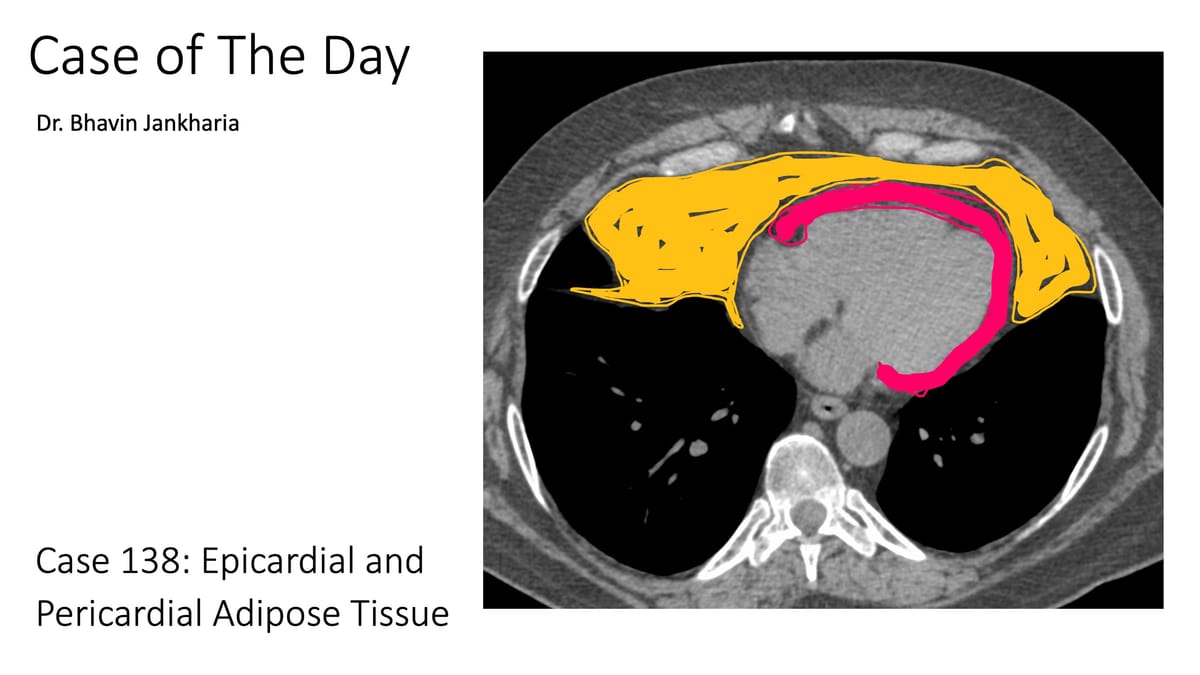

COD 138 - Epicardial and Pericardial Adipose Tissue

The correct terminology of epicardial vs pericardial adipose tissue versus fat pads